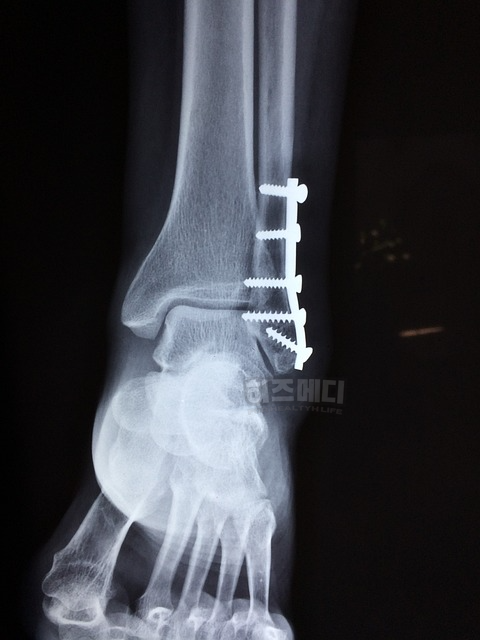

고관절은 대퇴골 경부(Neck)와 대퇴골 전체(Total) 부위를 측정합니다. 대퇴골 경부는 고관절과 허벅지뼈가 연결되는 목 같은 부분입니다. 이 부위는 몸의 무게를 많이 받기 때문에 약해지기 쉽고, 골절 위험이 큽니다.

대퇴골 전체는 고관절 부위 전체를 포함한 평균적인 뼈 밀도를 보여주기 때문에 고관절의 전체 상태를 파악할 수 있습니다. 대퇴골 경부와 전체 부위를 보는 것은 골절 위험을 더 정확히 판단하는 데 도움이 됩니다.

고관절의 대퇴골을 검사할 때도, 만약 고관절에 인공관절이 있거나 골절 등의 손상 이력이 있다면 제외합니다. 인공관절이나 비정상적인 뼈는 실제 뼈 밀도를 정확히 반영하지 않기 때문에 검사에 포함하지 않는 것이 원칙입니다.